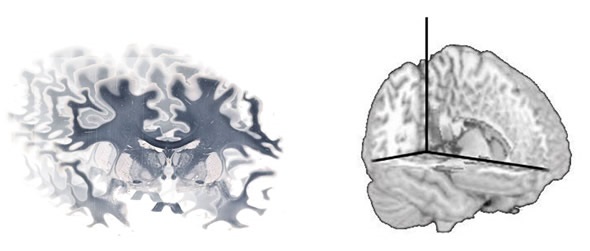

In addition, TissueScope™ can be used to acquire z-stacks and optical sections on specific ranges of tissue up to 500μm or even 2mm in depth using the appropriate clearing methods. Use of the optional TissueSnap™ workflow accessory avoids the need for pre-processing and preview scanning, meaning the main scanner can operate at full throughput and the time to view is further reduced. The scans performed using a Huron scanner are stored in non-proprietary, open .tiff format, which enables researchers to use a range of image analysis software to create 3D reconstructions of tissue (Figure 2).

Picture 2. A series of whole brain images can be reconstructed using software to produce a 3D volume. Image credit: Huron Digital Pathology.